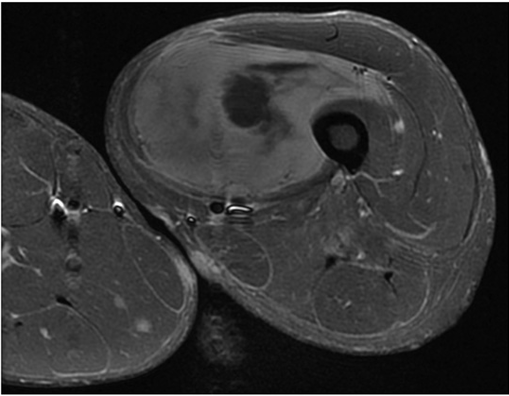

Hallazgo radiológico característico

4.1 RM con contraste: prueba principal

- T1: señal baja o intermedia.

- T2/STIR: señal alta y habitualmente heterogénea.

- Contraste: realce irregular de áreas sólidas; necrosis no captante.

- Signos de alarma: bordes mal definidos, necrosis, infiltración, edema, pérdida de rasgos típicos de benignidad.